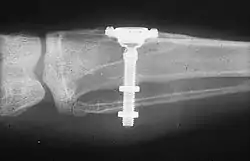

A dental implant (also known as an endosseous implant or fixture) is a prosthesis that interfaces with the bone of the jaw or skull to support a dental prosthesis such as a crown, bridge, denture, or facial prosthesis or to act as an orthodontic anchor. The basis for modern dental implants is a biological process called osseointegration, in which materials such as titanium or zirconia form an intimate bond to the bone. The implant fixture is first placed so that it is likely to osseointegrate, then a dental prosthetic is added. A variable amount of healing time is required for osseointegration before either the dental prosthetic (a tooth, bridge, or denture) is attached to the implant or an abutment is placed which will hold a dental prosthetic/crown.

Single tooth restorations are individual freestanding units not connected to other teeth or implants, used to replace missing individual teeth.[11] For individual tooth replacement, an implant abutment is first secured to the implant with an abutment screw. A crown (the dental prosthesis) is then connected to the abutment with dental cement, a small screw, or fused with the abutment as one piece during fabrication.[15]: 211–232 Dental implants, in the same way, can also be used to retain a multiple tooth dental prosthesis either in the form of a fixed bridge or removable dentures.

A typical conventional implant consists of a titanium screw (resembling a tooth root) with a roughened or smooth surface. The majority of dental implants are made of commercially pure titanium, which is available in four grades depending upon the amount of carbon, nitrogen, oxygen and iron contained.[21] Cold work hardened CP4 (maximum impurity limits of N .05 percent, C .10 percent, H .015 percent, Fe .50 percent, and O .40 percent) is the most commonly used titanium for implants. Grade 5 titanium, Titanium 6AL-4V (signifying the titanium alloy containing 6 percent aluminium and 4 percent vanadium alloy) is slightly harder than CP4 and used in the industry mostly for abutment screws and abutments.[22]: 284–285 Most modern dental implants also have a textured surface (through etching, anodic oxidation or various-media blasting) to increase the surface area and osseointegration potential of the implant.[23]: 55 If C.P. titanium or a titanium alloy has more than 85% titanium content, it will form a titanium-biocompatible titanium oxide surface layer or veneer that encloses the other metals, preventing them from contacting the bone.[24]

- Placement of the implant: The implant screw is placed and can be self-tapping,[32]: 100–102 otherwise the prepared site is tapped with an implant analog. It is then screwed into place with a torque controlled wrench[36] at a precise torque so as not to overload the surrounding bone (overloaded bone can die, a condition called osteonecrosis, which may lead to failure of the implant to fully integrate or bond with the jawbone).

An abutment is selected depending on the application. In many single crown and fixed partial denture scenarios (bridgework), custom abutments are used. An impression of the top of the implant is made with the adjacent teeth and gingiva. A dental lab then simultaneously fabricates an abutment and crown. The abutment is seated on the implant, a screw passes through the abutment to secure it to an internal thread on the implant (lag-screw). There are variations on this, such as when the abutment and implant body are one piece or when a stock (prefabricated) abutment is used. Custom abutments can be made by hand, as a cast metal piece or custom milled from metal or zirconia, all of which have similar success rates.[32]: 1233

The platform between the implant and the abutment can be flat (buttress) or conical fit. In conical fit abutments, the collar of the abutment sits inside the implant which allows a stronger junction between implant and abutment and a better seal against bacteria into the implant body. To improve the gingival seal around the abutment collar, a narrowed collar on the abutment is used, referred to as platform switching. The combination of conical fits and platform switching gives marginally better long term periodontal conditions compared to flat-top abutments.[53]